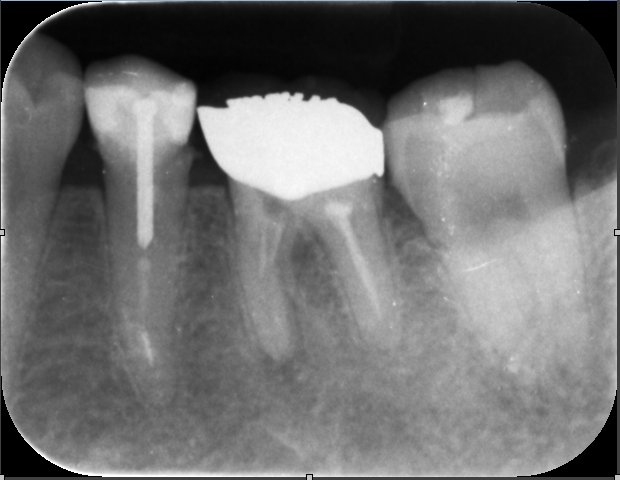

主訴:他院で1年根管治療していて不安。治らない。むむっ。根管充填が不良。これは痛そう。

精密根管治療で綺麗に。

根管充填 これでよくなるはずです。来年おいしいものを沢山食べれる様に!!